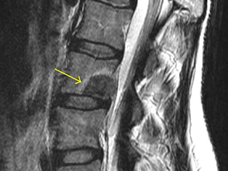

For some patients with painful spinal metastases from advanced cancer, a type of precise, high-dose radiation therapy—called stereotactic body radiation therapy (SBRT)—may be a highly effective way to relieve that pain, clinical trial results show.